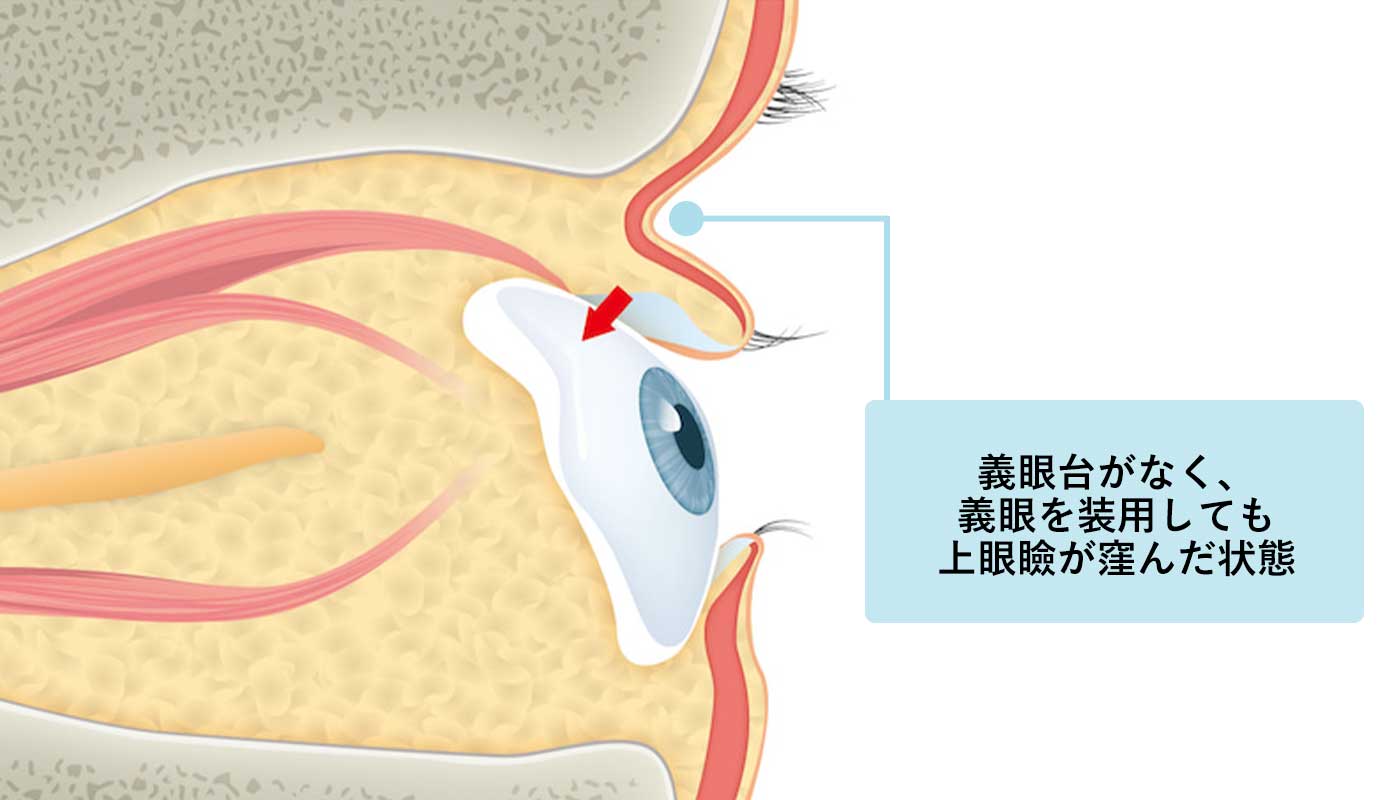

義眼台がなく、

上眼瞼が窪んだ状態

眼球の容積が減少している、もしくは摘出されていると、眼窩全体が落ち込み、特に上のまぶたの凹みとなって表れます。